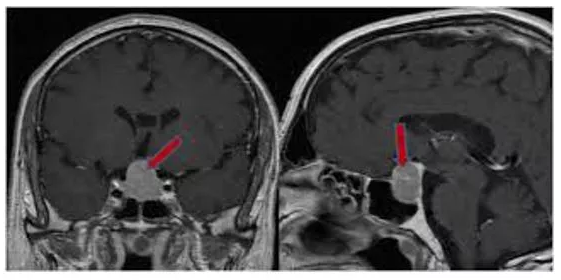

Hipofiz Adenomları

Hipofiz adenomları çoğunlukla iyi huylu tümörler olup kafatasının tabanında ve beynin altında yerleşmiş olan hipofiz bezinden kaynakla...